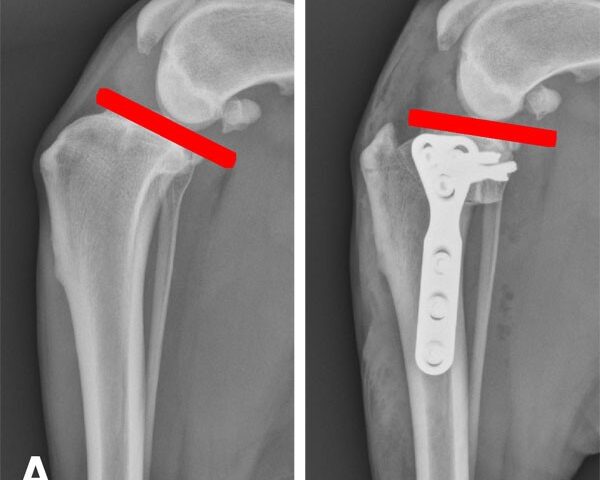

O tratamento para a ruptura de ligamento em cães pode variar de acordo com a gravidade da lesão. Em casos leves, os veterinários podem recomendar repouso, medicação para dor e fisioterapia. Em casos mais graves, o tratamento pode envolver cirurgia para reconstruir o ligamento ou estabilizar a articulação do joelho.